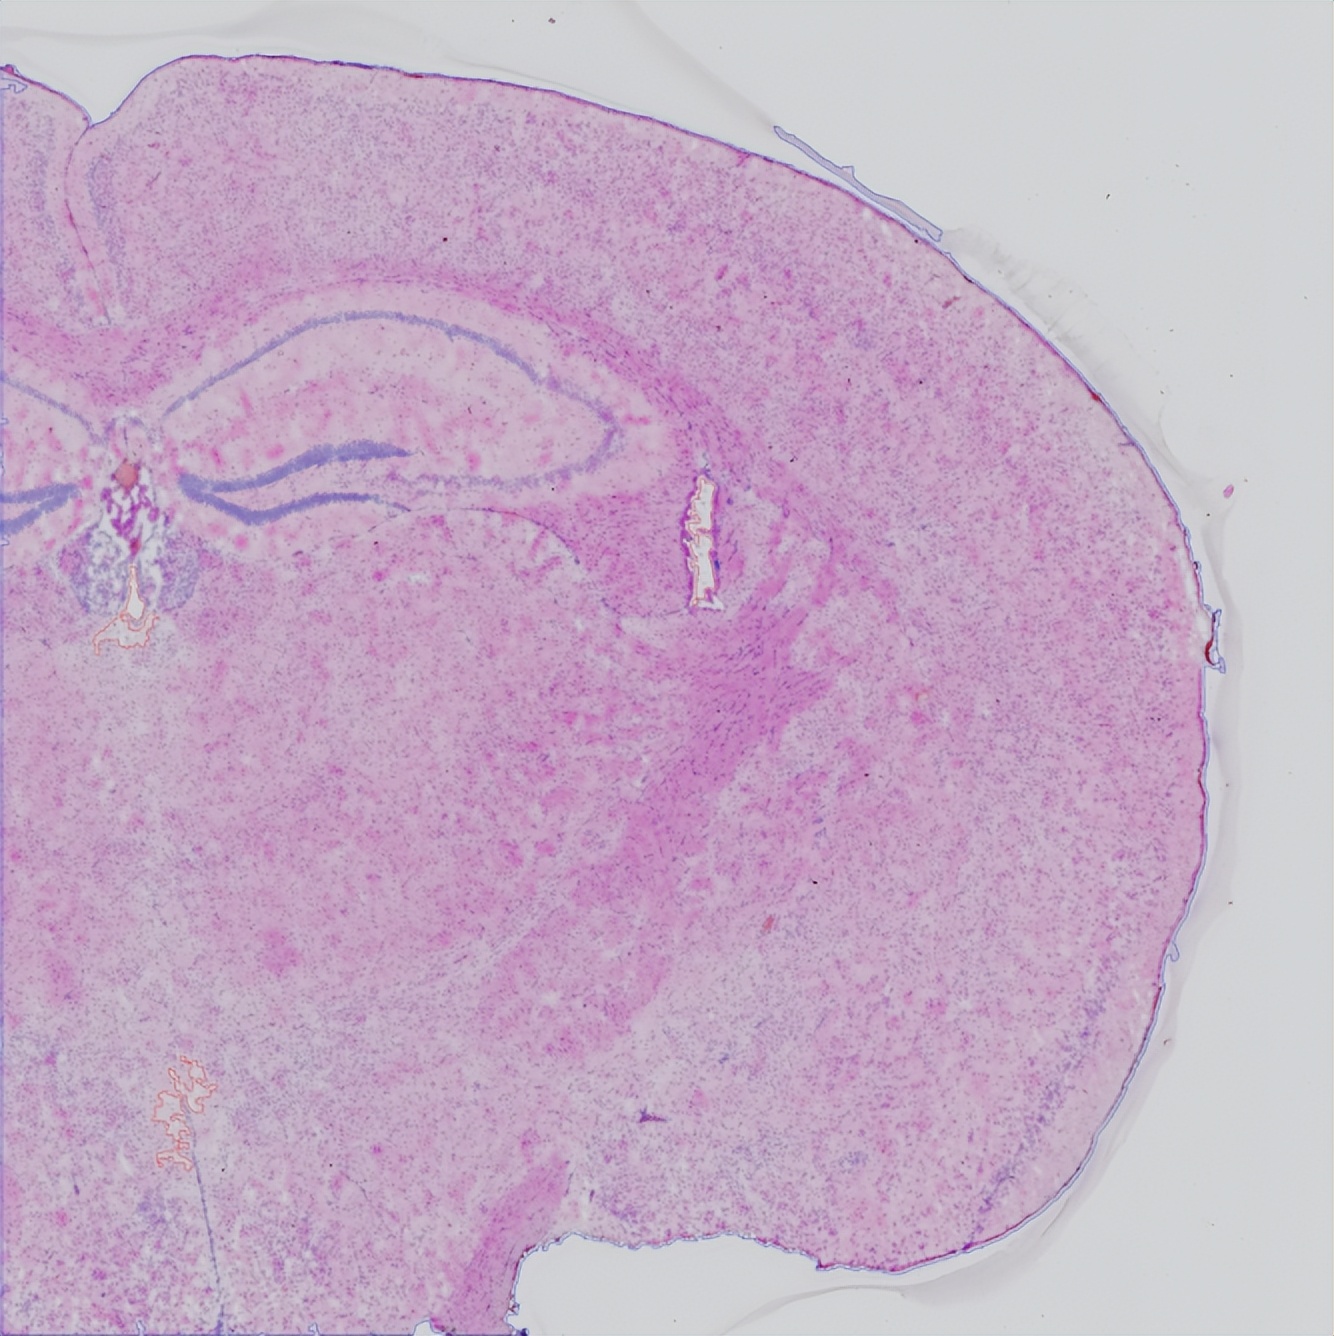

在肿瘤、大脑、免疫器官等高度异质性的组织中,细胞类型繁多且功能状态多样。空间ATAC-seq能够在不破坏组织结构的条件下,区分不同细胞类型(如癌细胞、免疫细胞、基质细胞)特有的染色质开放特征。在小鼠大脑皮层发育过程中,研究发现皮质层特异性转录因子(如Bhlhe22、Fezf2、Tbr1)表现出独特的染色质可及性时空模式。例如,Fezf2和Tbr1的RNA表达被严格限制在特定皮质层,但其基因可及性评分(GAS)却扩展到更广泛的区域。这表明,尽管染色质处于开放状态,但Polycomb介导的表观遗传抑制机制可能防止这些层特异性基因的异位表达2。

在BMKMANU S3000-ATAC Demo中也有一致的结论:

Fezf2和Tbr1的RNA表达被严格限制在特定皮质层,但其基因可及性评分(GAS)却扩展到更广泛的区域

Species Information: Mouse brain